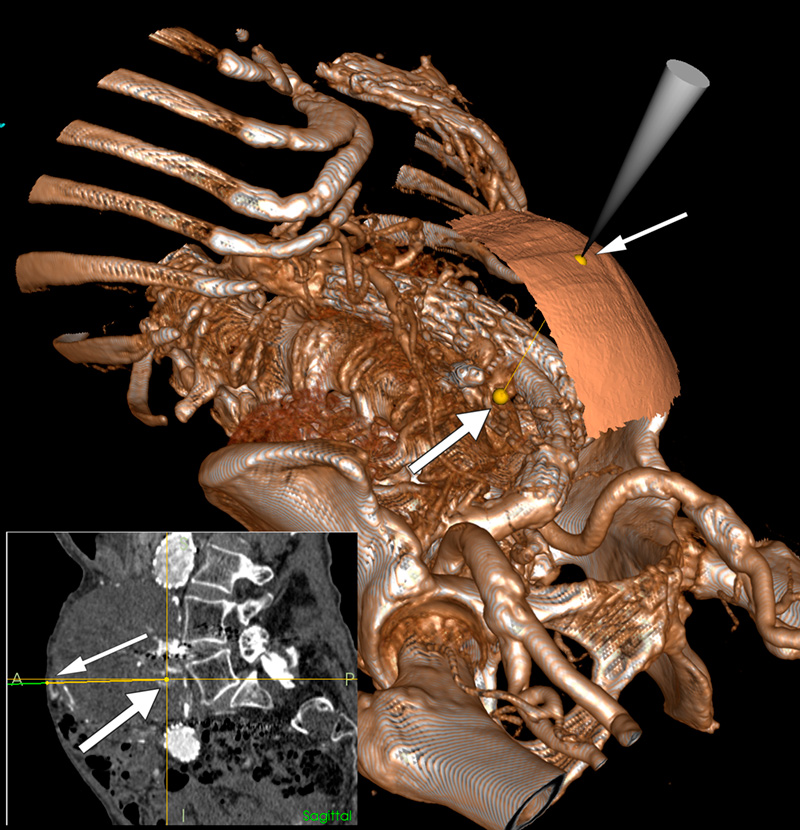

Nasjonalt kompetansesenter for ultralyd og bildeveiledet behandling har utviklet et navigasjonssystem (1) som kontinuerlig viser posisjonen til forskjellige instrumenter i et 3D-bilde. I en gjennomlysningsstue med integrert 3D-avbildningsutstyr kunne det ved hjelp av navigasjonssystemet utføres perkutan embolisering uten å måtte flytte pasienten. Stor figur viser et 3D-bilde av pasienten med nåletuppens plassering på hudoverflaten (tynn pil) og retning mot en av lumbalarteriene (tykk pil). Slik kan nålen plasseres optimalt og posisjonen kontrolleres underveis med mulighet for flere innstikk basert på samme bildeopptak. Liten figur viser samme oppsett i sagittalplanet. Mikrokateteret ble anlagt via nålen og lumbalarteriene embolisert med Onyx-injeksjoner. Kontroll halvannet år senere viste ingen lekkasje og uendret størrelse på aneurismet. Metoden er eksperimentell og del av et pågående forskningsprosjekt.